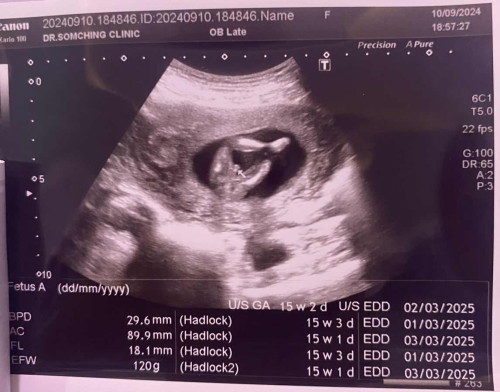

ถามแม่ๆหน่อยคะน้องจะเป็นผู้ชายไหมค่ะ#ขอบคุณสำหรับคำคอมเม้นล่วงหน้าค่ะ

คุณหมอบอกอาจจะผู้ชายแล้วก็พูดลอยๆว่าชาย

ผู้ชายค่ะ ตรงที่ลูกศรชี่เหมือนจะเป๋นจู๋น้อง